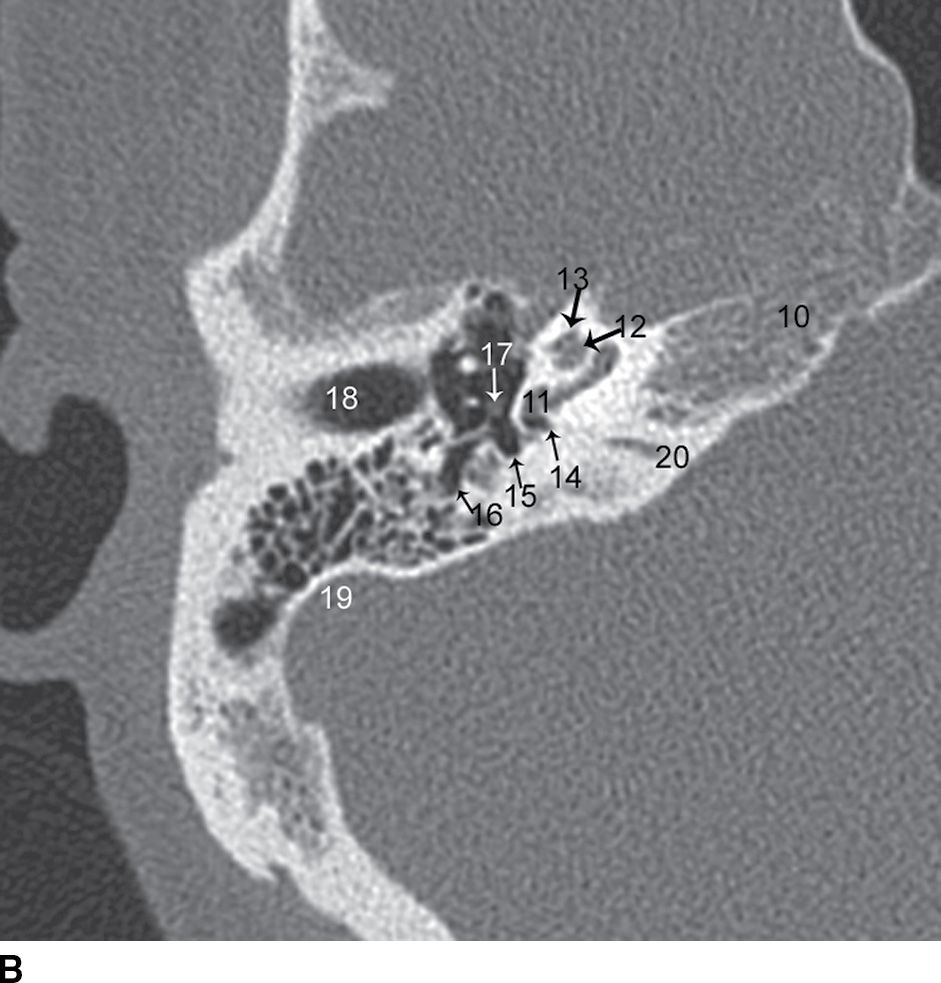

Coronal CT images show the normal anatomy of the temporal bone from

Coronal CT images show the normal anatomy of the temporal bone from Ct Anatomy Of Temporal Bone Some structures are discussed in more detail with emphasis on related. In this review we present the normal axial and coronal anatomy of the temporal bone by scrolling through the images. Several intrinsic channels, intrinsic fissures, and extrinsic sutures are often apparent on ct images and can mimic fractures (pseudofractures) (1). We have created an atlas of the temporal bone,. Ct Anatomy Of Temporal Bone.